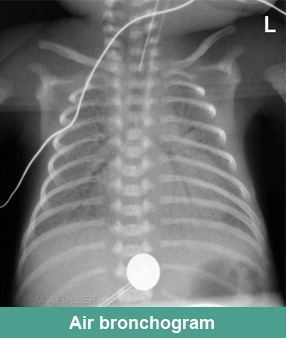

7. Typical X-ray finding of RDS/ HMD

► Decreased lung volume

► Reticulogranular pattern

► Ground glass opacification

► Air bronchograms

► White out lungs